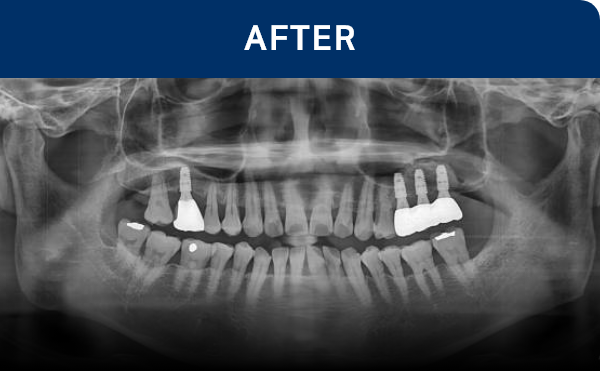

전후가 명확한 결과, 그 결과가

곧 신길플란트치과의 신뢰입니다.